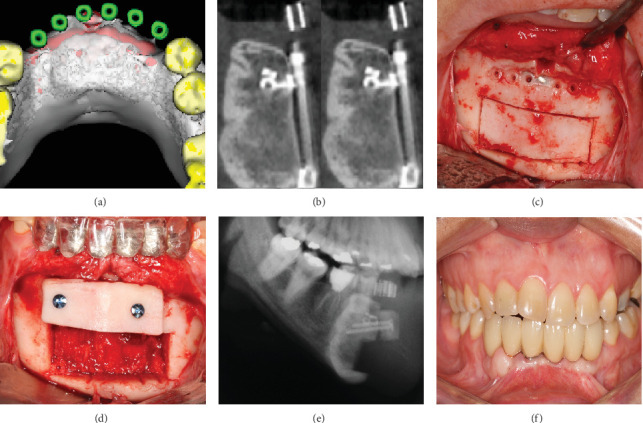

目的:本病例报告详细介绍了一名28岁女性前下颌弓复发性中央巨细胞肉芽肿(CGCG)的长期治疗。病例报告:在2007年首次手术切除后,导致明显的骨缺损,采用多学科方法恢复下颌完整性和功能。2009年,使用DePuy Synthes牙槽牵张器进行牙槽牵张成骨。随后,在2011年进行了自体上牙体植骨,以优化牙槽嵴轮廓。2012年放置了4个Neodent CM植入物,随后进行了假肢康复。2024年的15年随访显示了良好的结果,种植体周围组织稳定,骨水平维持正常,假体功能齐全。本病例强调了包括牵张成骨和自体植骨在内的先进手术技术在治疗复杂CGCG病例中的疗效。结果和结论:成功的长期结果强调了综合治疗方法和定期随访对解决侵袭性和复发性cgcg带来的挑战的重要性。本报告提供了有价值的见解,在广泛的CGCG治疗后,全面功能和美学修复的潜力,强调了在颌面重建中良好协调的多学科方法的好处。

Aim: This case report details the long-term management of a recurrent central giant cell granuloma (CGCG) in the anterior mandibular arch of a 28-year-old female. Case Report: Following initial surgical resection in 2007, which resulted in a significant bony defect, a multidisciplinary approach was employed to restore mandibular integrity and function. In 2009, alveolar distraction osteogenesis was performed using a DePuy Synthes alveolar distractor. Subsequently, in 2011, autogenous onlay bone grafting was carried out to optimize the alveolar ridge contour. Four Neodent CM implants were placed in 2012, followed by prosthetic rehabilitation. The 15-year follow-up in 2024 revealed excellent outcomes, with stable peri-implant tissues, maintained bone levels, and a fully functional prosthesis. This case highlights the efficacy of combining advanced surgical techniques, including distraction osteogenesis and autogenous bone grafting, in managing complex CGCG cases. Results and Conclusion: The successful long-term outcome underscores the importance of a comprehensive treatment approach and regular follow-up in addressing the challenges posed by aggressive and recurrent CGCGs. This report provides valuable insights into the potential for fully functional and aesthetic restoration following extensive CGCG treatment, emphasizing the benefits of a well-coordinated, multidisciplinary approach in maxillofacial reconstruction.